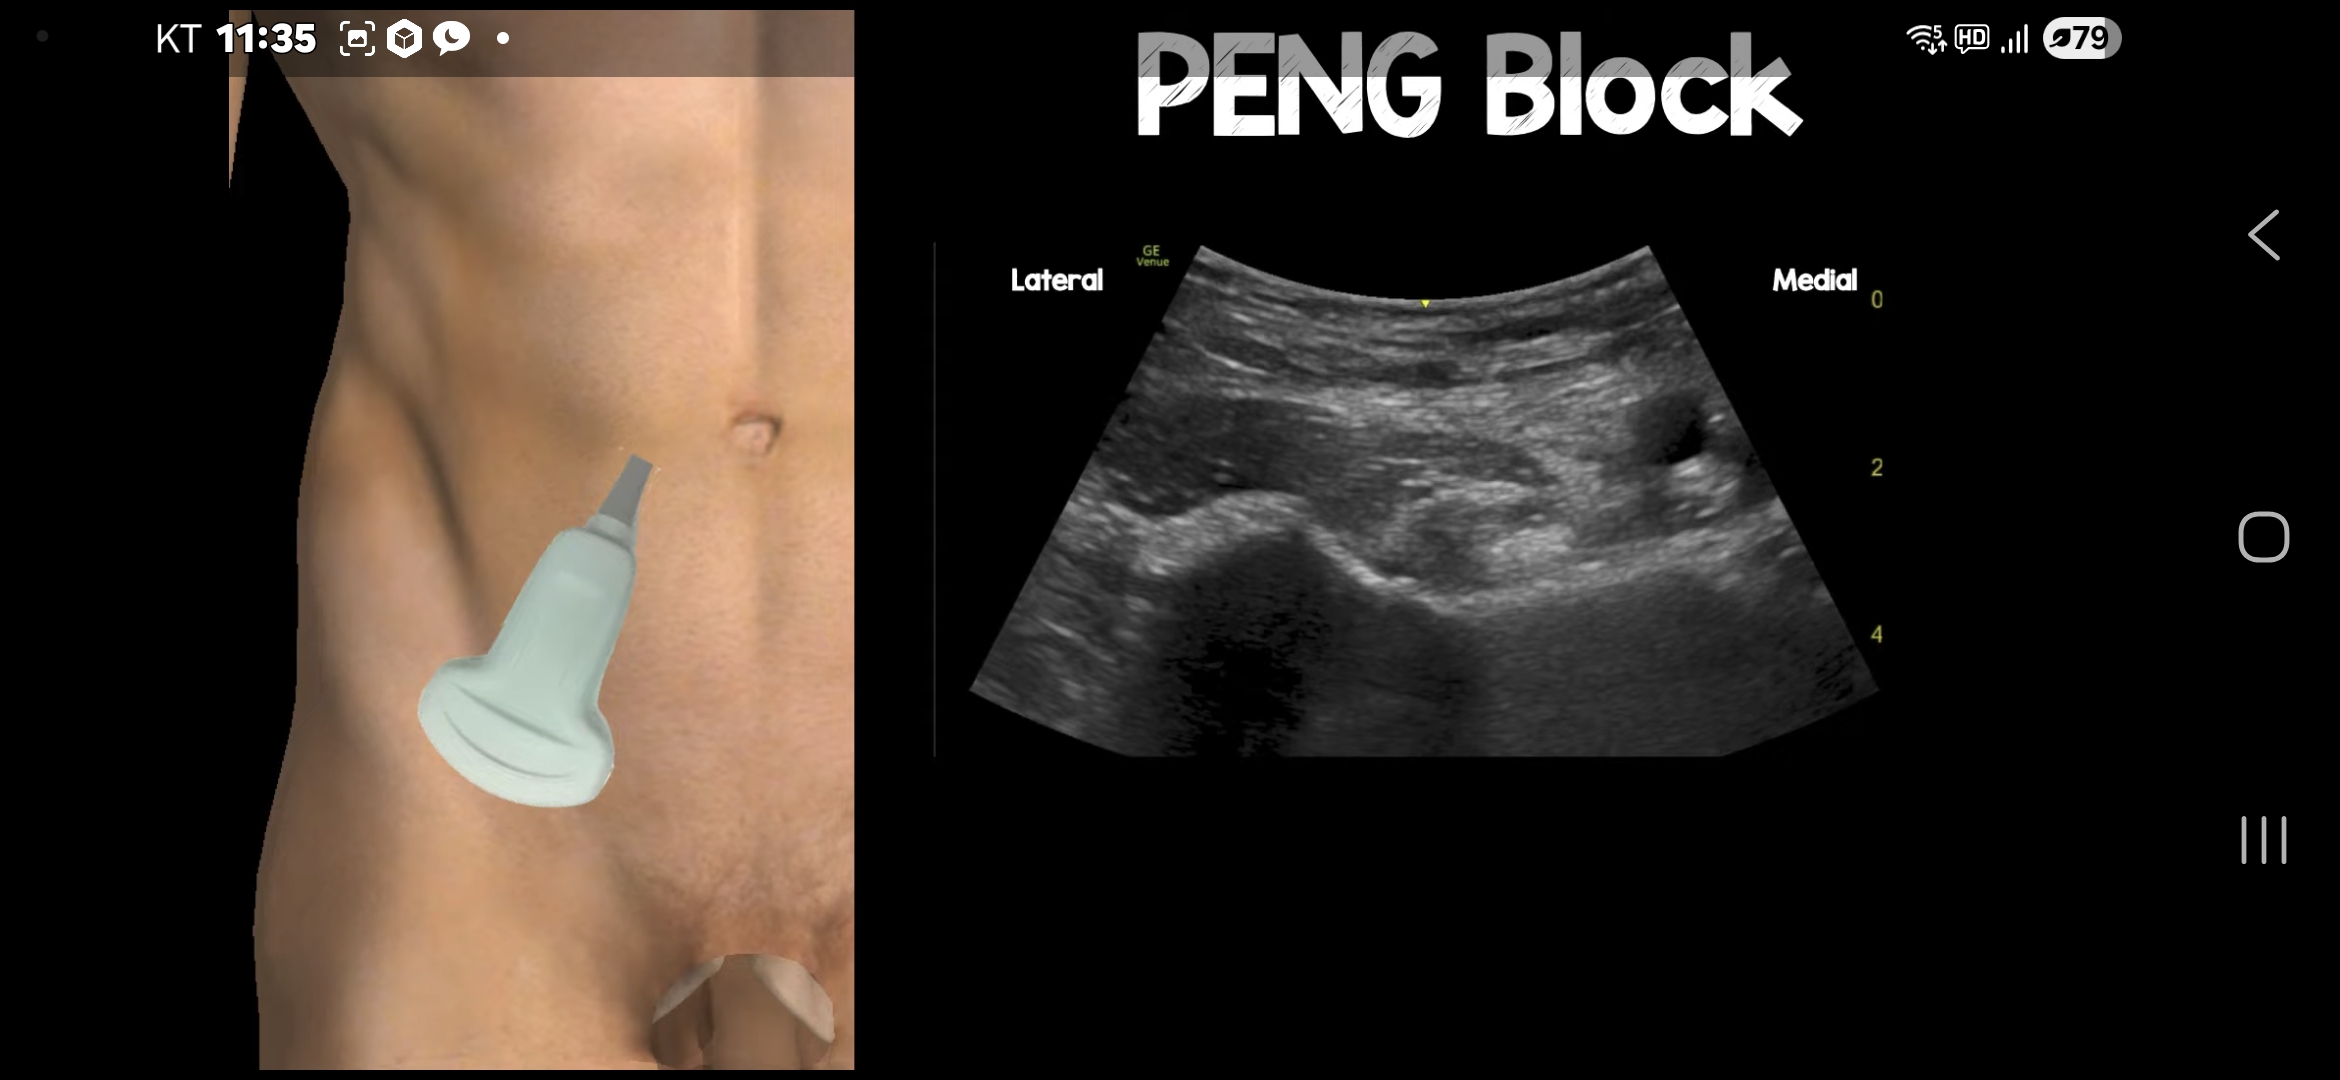

1. Pericapsular Nerve Group(PeNG) block

읽어 보니 사용한 방법은 두가지 신경 차단술이었다.

하나는 몇년 전부터 고관절 통증 관리, 특히 고관절 수술 후 통증 관리에 사용한 방법이고, 다른 하나는 내가 아는 신경 차단술이었다.

I. PeNG block

PeNG block + LFCN block